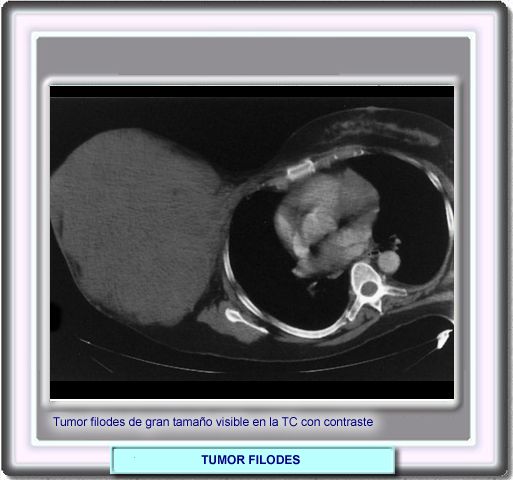

Aunque no se utiliza a menudo por sus elevados costes y las molestias que representa para la paciente, la TC muestra los tumores filodes como masas homogéneas bien delimitadas como en este caso, en el que el tumor ha alcanzado un tamaño > 30 cm.